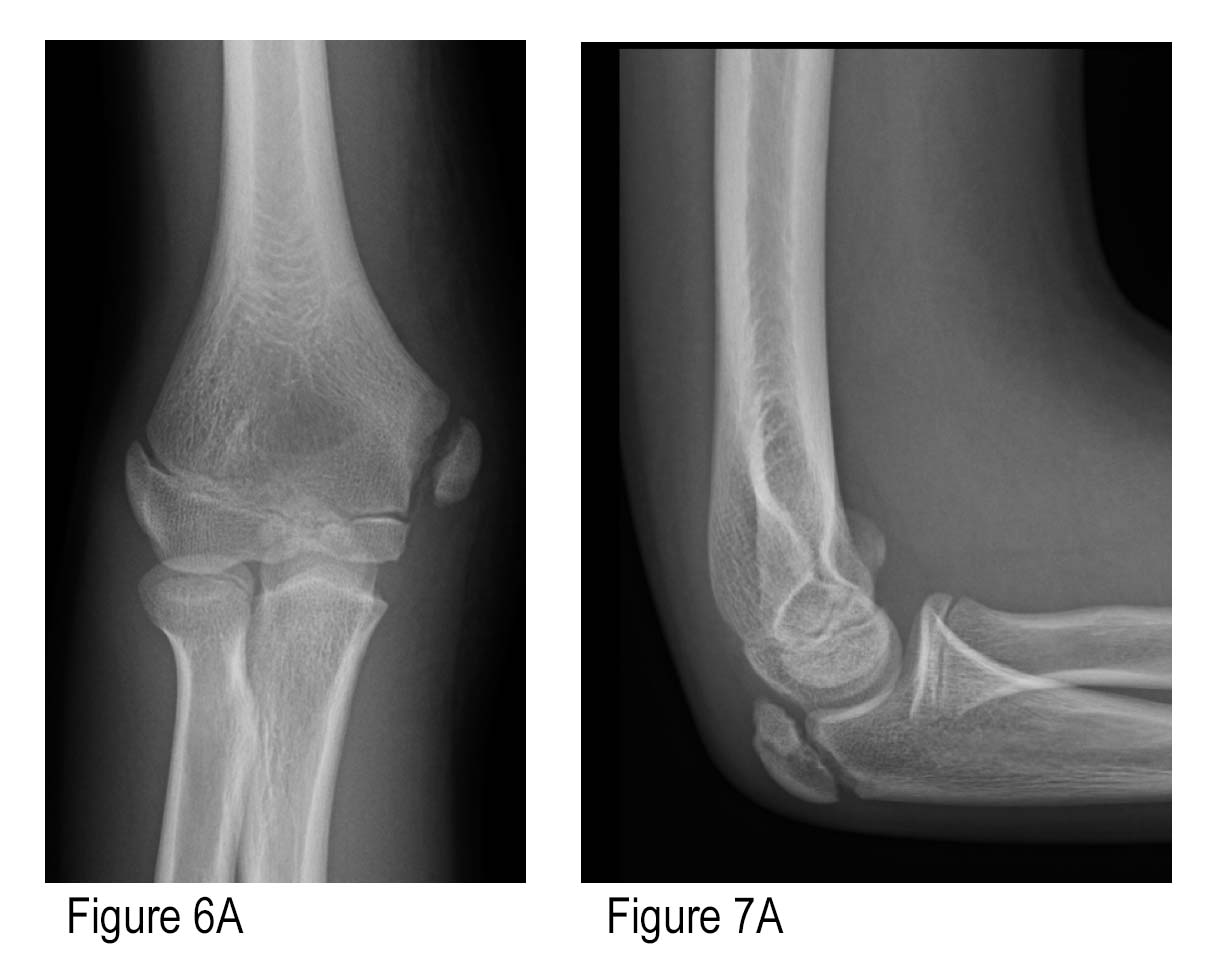

X Ray Elbow

Elbow x-ray - labelling questions | Radiology Case | Radiopaedia.org Anatomy of Elbow X-rays - YouTube Elbow series | Radiology Reference Article | Radiopaedia.org EMRad: Radiologic Approach to the Pediatric Traumatic Elbow X-ray | X Ray Elbow